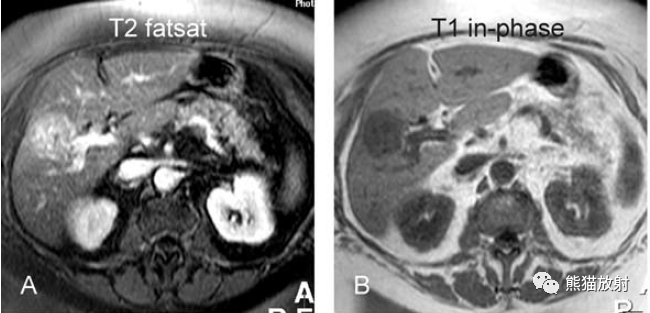

T2壓脂(T2 fatsat):膽囊窩內(nèi)膽囊癌病變較肝臟為高信號(hào),病變頂部向肝內(nèi)擴(kuò)展;

T1同相位(T1 in-phase):膽囊癌病變較肝臟為低信號(hào);

膽囊癌。A~D圖:上方層面,表現(xiàn)如上所述,形成腫物侵及肝臟。E、F圖:下方層面示膽囊壁不規(guī)則增厚,明顯不均質(zhì)強(qiáng)化。